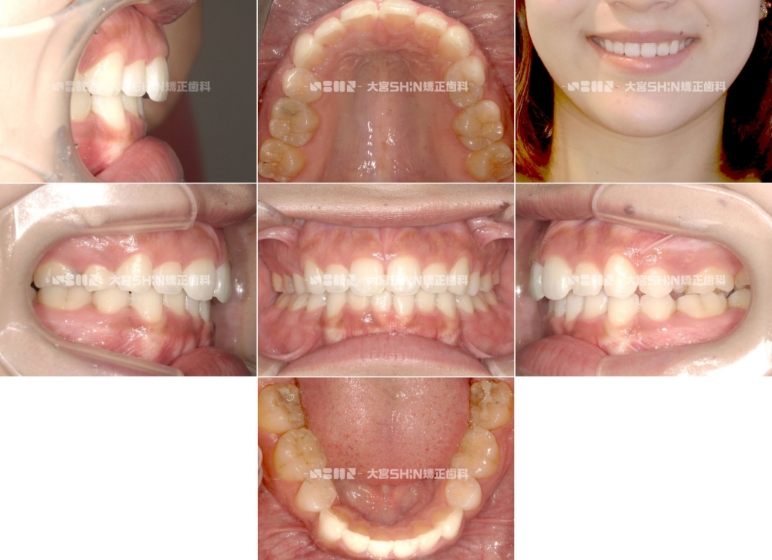

症例2:

かみ合わせが深い歯並び(過蓋咬合)を改善してガミースマイルも改善された症例

主訴 ガタガタ、前歯のかみ合わせ、ガミースマイルが気になる

診断名 過蓋咬合

初診時年齢 28歳

装置名 マウスピース矯正装置(インビザライン)、矯正用アンカースクリュー2本

抜歯部位 なし

治療期間 3年

費用 ¥925,000(税込¥1,017,500)

リスク・副作用 痛み、歯根吸収、歯肉退縮、虫歯、後戻り

治療のポイント 過蓋咬合が原因でガミースマイルの場合、前歯部の上方への垂直的な圧下を促すことで、歯茎が見えづらくなります。

Before

After